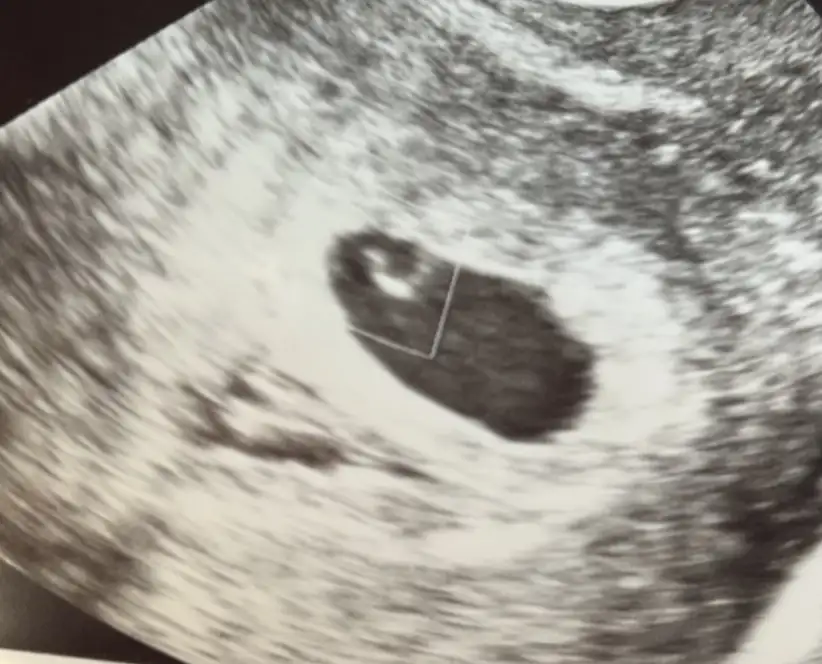

Iron Butterfly Iron Butterfly canım çok sevindim inş darısı kalp atışına bende bugün keseyi gördüm 😍😍

Evet canısı verdim 2915 çıktı Perşembe kese için çağırdılar 5 hafta 1 günlük olmuşum 💕💕

• IMG_20231219_095833.webp

IMG_20231219_095833.webp

23,4 KB · Görüntüleme: 45